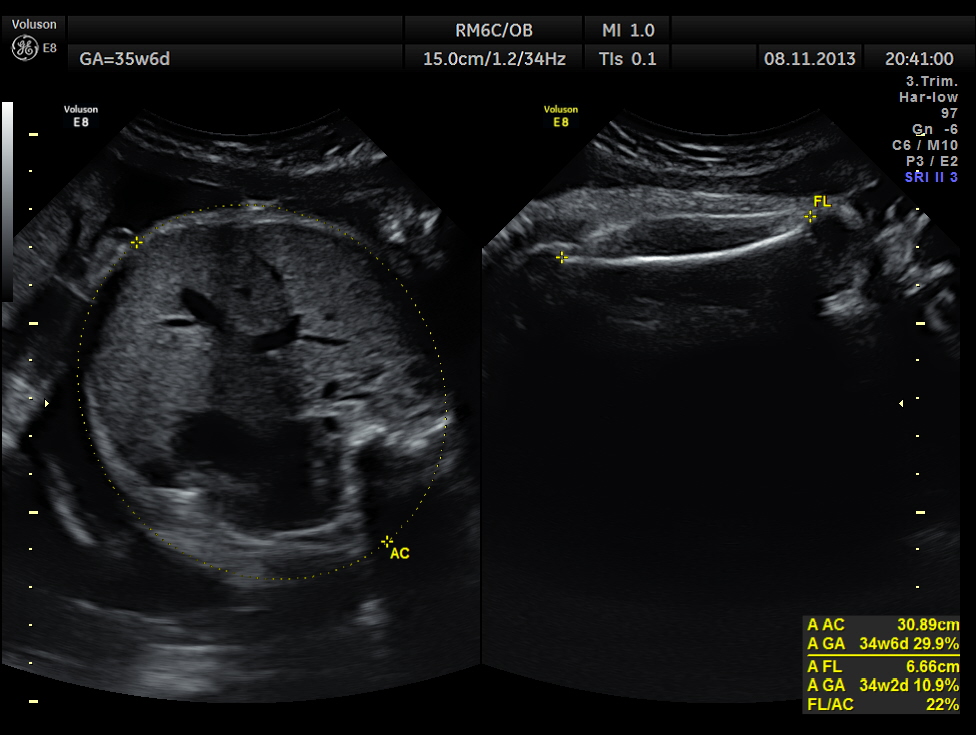

The scan was repeated at 36 weeks of gestation.

AC and FL appear to be normal.

the umbilical artery doppler appears normal.

The overlapping skull bones of the fetus ,which died earlier .